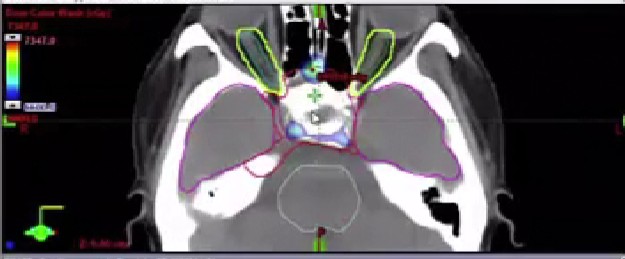

12/29/2025 - Dr. David Sher - Radiation Oncology - Head & Neck